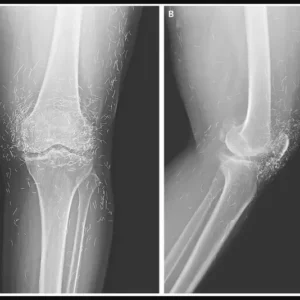

X-Ray Reveals Hundreds of Gold Needles in Woman’s Knees

Doctors examining X-rays of a 65-year-old South Korean woman with severe knee pain made a startling discovery: hundreds of tiny gold acupuncture needles embedded in her tissue….